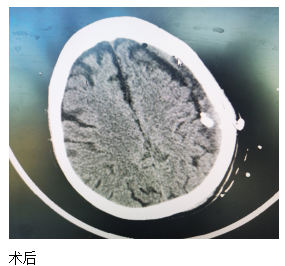

近日,一位84歲高齡患者來江寧中院就診,表現(xiàn)為:右側(cè)肢體的力量下降、不能獨(dú)立站立、言語不利、吐字不清。經(jīng)頭部CT檢查發(fā)現(xiàn),患者左側(cè)大面積慢性硬膜下血腫,嚴(yán)重壓迫腦組織。

患者收入院后,完善各項(xiàng)檢查,無明顯手術(shù)禁忌,中醫(yī)院神經(jīng)外科團(tuán)隊(duì)經(jīng)過精心周全的準(zhǔn)備,為其實(shí)施了腦膜中動脈栓塞結(jié)合硬通道血腫穿刺引流的復(fù)合手術(shù)。術(shù)后第二天,患者肢體無力的癥狀得到了明顯改善,語言表達(dá)也恢復(fù)如初?;颊呒凹覍賹Υ酥委熜Ч浅M意。